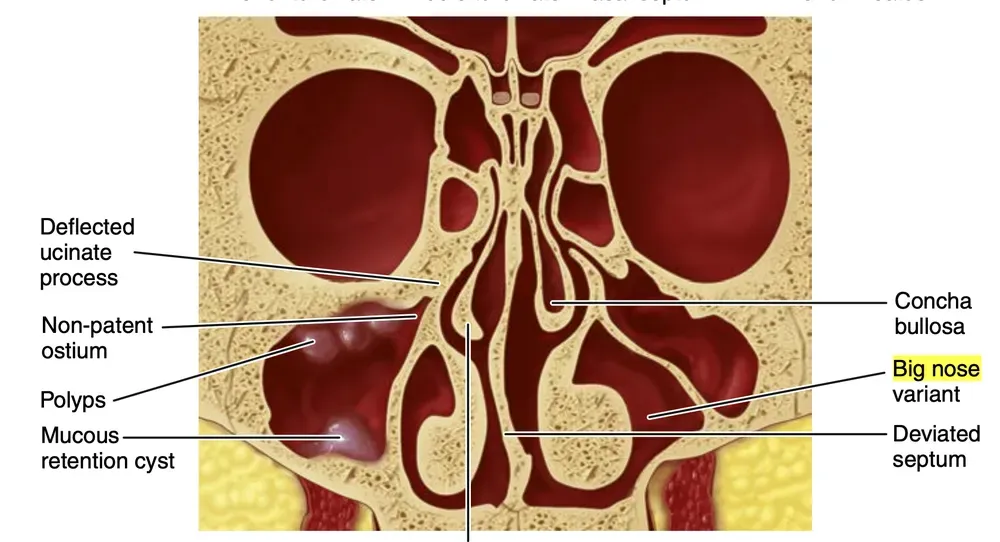

Figura della variante big nose tratta da  Misch, Contemporary Implant Dentistry

Da Misch, Contemporary Implant Dentistry.

Nel “big-nose”, la pneumatizzazione del terzo inferiore della cavità nasale verso l’interno della cresta alveolare sposta lateralmente il margine distale del seno mascellare. Il naso si allarga, mentre il seno mascellare si stringe.